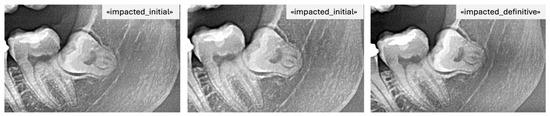

- Partially impacted: the occlusal surface was below the occlusal plane but partially exposed, with part of the crown still covered by alveolar bone or showing limited eruption space between the distal of the second molar and the anterior border of the ramus.

- Impacted: the third molar was entirely below the occlusal plane, with full bone coverage and/or evident spatial limitation or unfavorable angulation (e.g., mesioangular or horizontal position) in relation to the second molar.